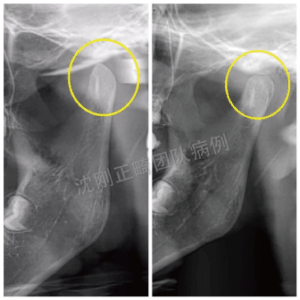

El reposicionamiento mandibular funciona restaurando terapéuticamente una mandíbula desplazada a su posición correcta y corrigiendo la oclusión causada por la malposición mandibular, logrando así una relación cúspide-fosa ideal. Es importante destacar que el reposicionamiento mandibular (incluido el avance mandibular) modifica la posición de la mandíbula, no su tamaño, y no requiere un crecimiento adicional de la misma.

En su esencia se encuentra un fenómeno fisiológico conocido como remodelación adaptativa del cóndilo.

Esta remodelación se desencadena por fuerzas mecánicas que actúan sobre el tejido conectivo que recubre el cóndilo. Estas fuerzas estimulan a las células mesenquimales para que se diferencien en precondrocitos, iniciando la osteogénesis endocondral, un proceso biológicamente impulsado que sustenta el éxito del método de Smartee.